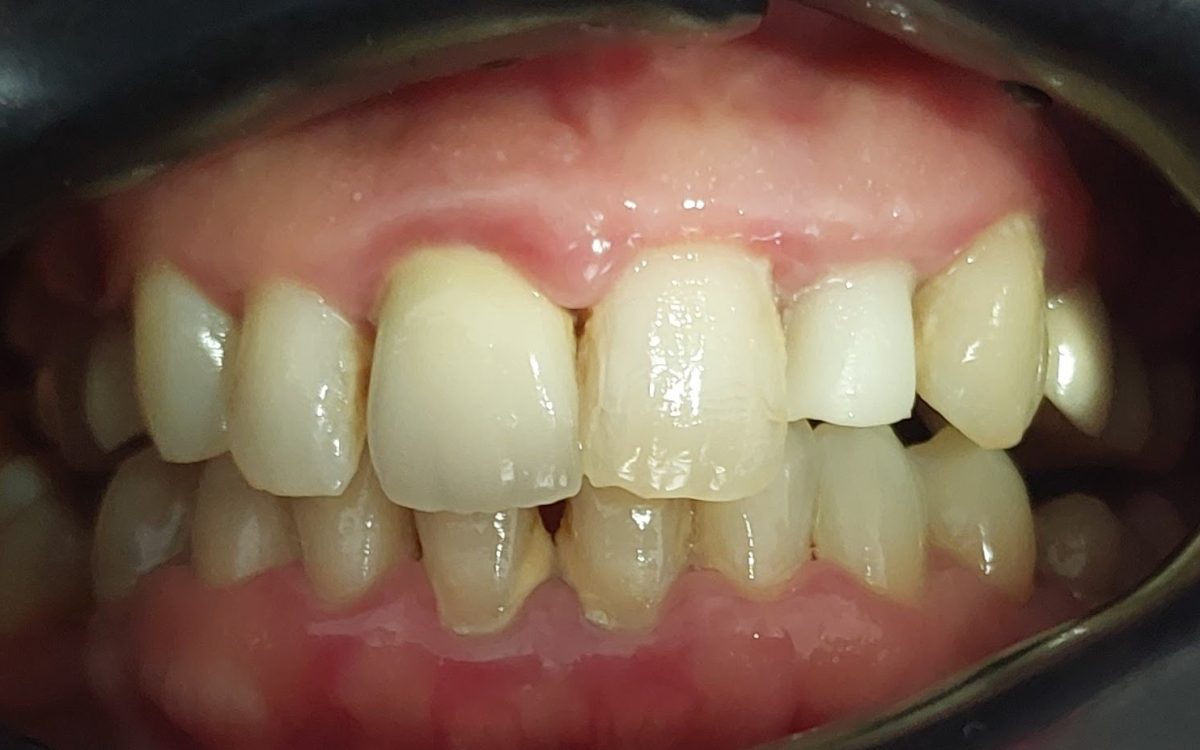

Fogászati korona

Hiányzó, sérült, vagy szuvasodott fogak pótlásának, helyreállításának egyik hagyományos és igen elterjedt eszköze a fogkorona.

Teljes porcelán, préskerámia korona

Fémmentes fogpótlás, cirkon korona

Porcelán (fémkerámia) fogkorona

Préskerámia korona:

- A préskerámia korona kiemelkedő esztétikájával tökéletesen illeszkedik a saját fogak közé, róla még közelről nézve sem mondható el, hogy fogpótlással állunk szemben!

- Elsősorban frontfogak (metszőfogak) helyreállítására alkalmazzuk, akár gyökérkezelt fogak esetén is. Mivel a préskerámia korona váza is fogszínű, ezért erősen elszíneződött gyökérkezelt fog esetén elsőként belső fogfehérítést kell végeznünk.

- Elsősorban szólókoronát készítünk belőle, híd készítéséhez inkább a cirkonkoronát javasoljuk.

- fémmentes, ezért fémallergiásoknak is javasoljuk

- anyaga préselt porcelán, mely tartós, akár kemény ételeket (répa, dió) is bátran lehet vele harapni

- előkészítéséhez minimális foganyag veszteséggel kell csak számolni (1 mm)